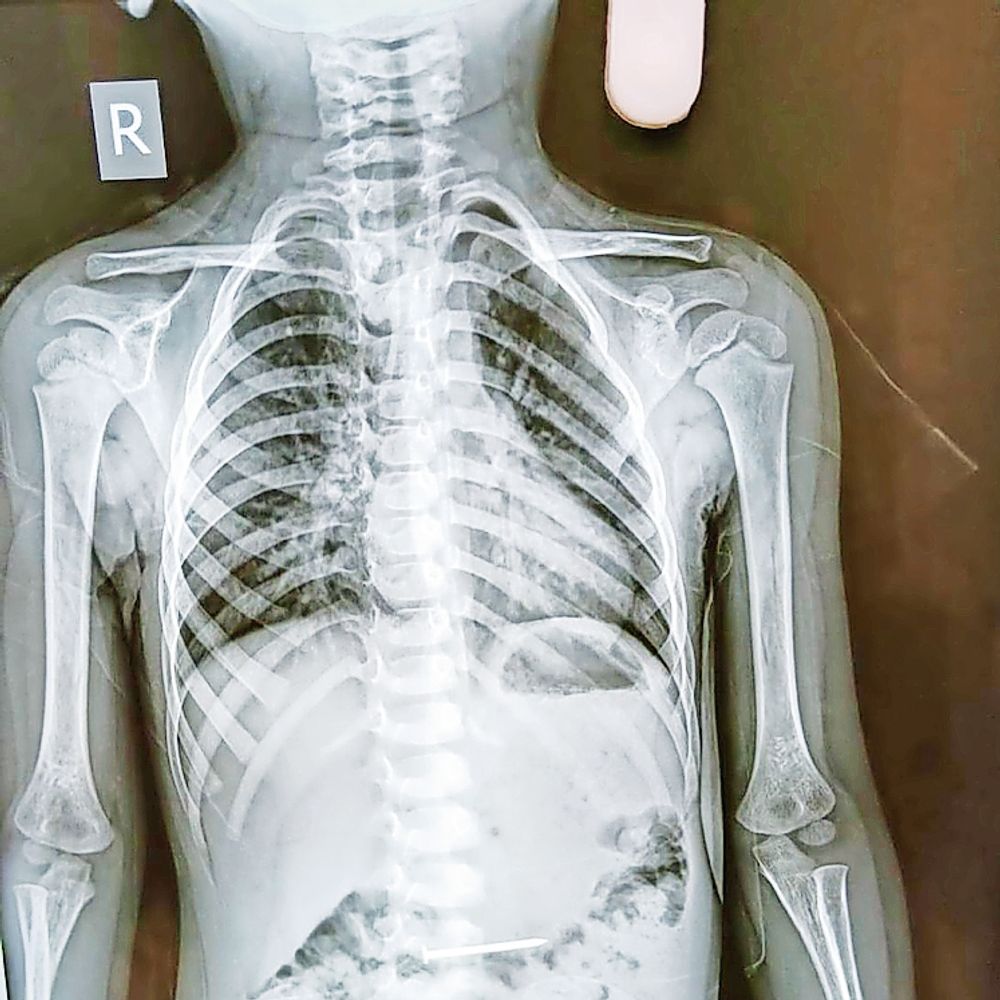

શ્રીમદ્ રાજચંદ્ર હોસ્પિટલ દ્વારા ચાર બાળકોને નવજીવન.

સુરેન્દ્રનગરની શ્રીમદ્ રાજચંદ્ર હોસ્પિટલમાં બાળકો દ્વારા ગળી ગયેલી વસ્તુઓના ચાર કેસમાં સફળ એન્ડોસ્કોપી સારવાર અપાઈ. ડોક્ટર્સની ટીમે લોહચુંબક, બટન, ખિલ્લી, સિક્કા જેવી વસ્તુઓ કાઢી. સમયસર નિદાન અને એન્ડોસ્કોપિક ટેક્નિકથી બાળકોને બચાવ્યા. હોસ્પિટલની સુવિધા દર્દીઓ માટે life saver સાબિત થઇ છે.

શ્રીમદ્ રાજચંદ્ર હોસ્પિટલ દ્વારા ચાર બાળકોને નવજીવન.